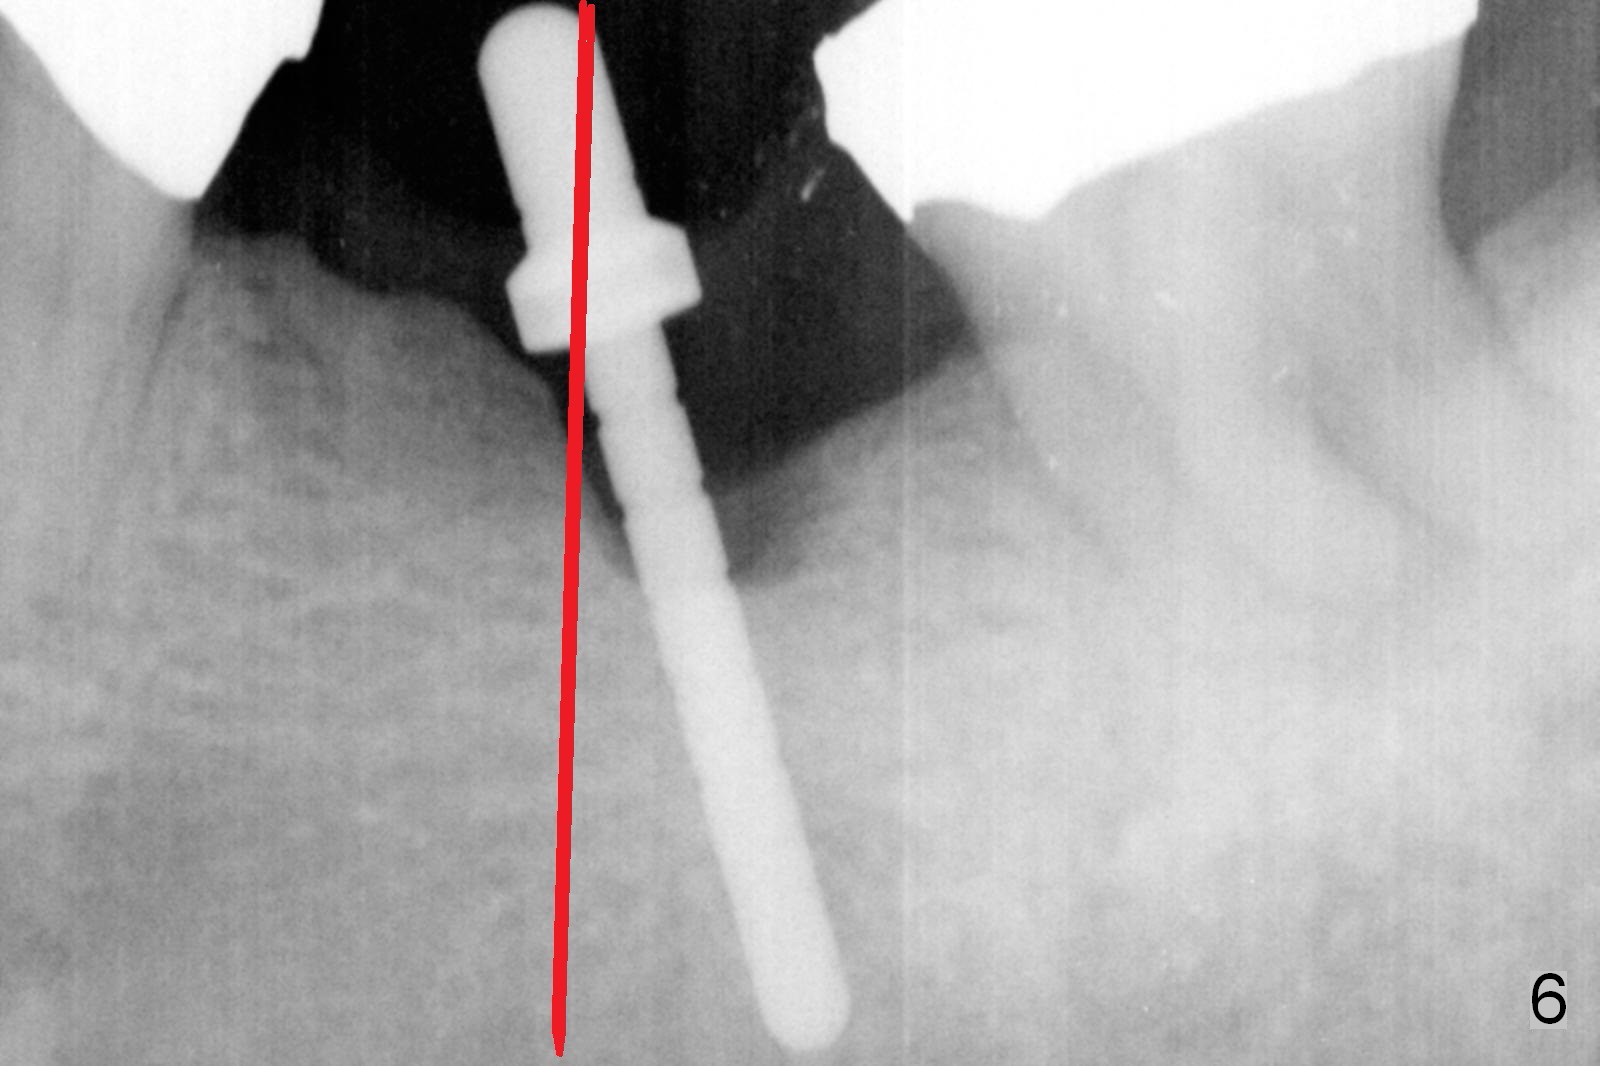

The narrow ridge top is trimmed until the buccolingual width is 7-8 mm; osteotomy starts in the flattened ridge (Fig.1, 2). A 5x10 mm implant is being placed (Fig.3). A cemented abutment (6.5x5.5(5) mm) is placed after adjusting the mesial and distal walls of the trimmed ridge (Fig.4). The patient returns for restoration 6 months postop. The coronal opening of the osteotomy becomes flared (Fig.5). The position and trajectory of the osteotomy should have been changed as early as possible (Fig.6, more or less parallel to the premolar) to avoid necessity of changing the cemented abutment (Fig.7 (* keratinized gingiva)) to an angled one (5.5 x15 degree A (4) mm).